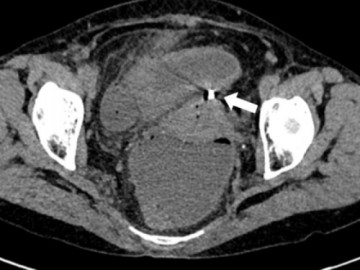

Vòng tránh thai 30 năm lạc chỗ đâm thủng ruột non

Quảng Ninh - Đặt vòng tránh thai hơn 30 năm, người phụ nữ 66 tuổi đau bụng dữ dội, bác sĩ phát hiện chiếc vòng lạc chỗ, đâm thủng ruột non gây viêm nặng.